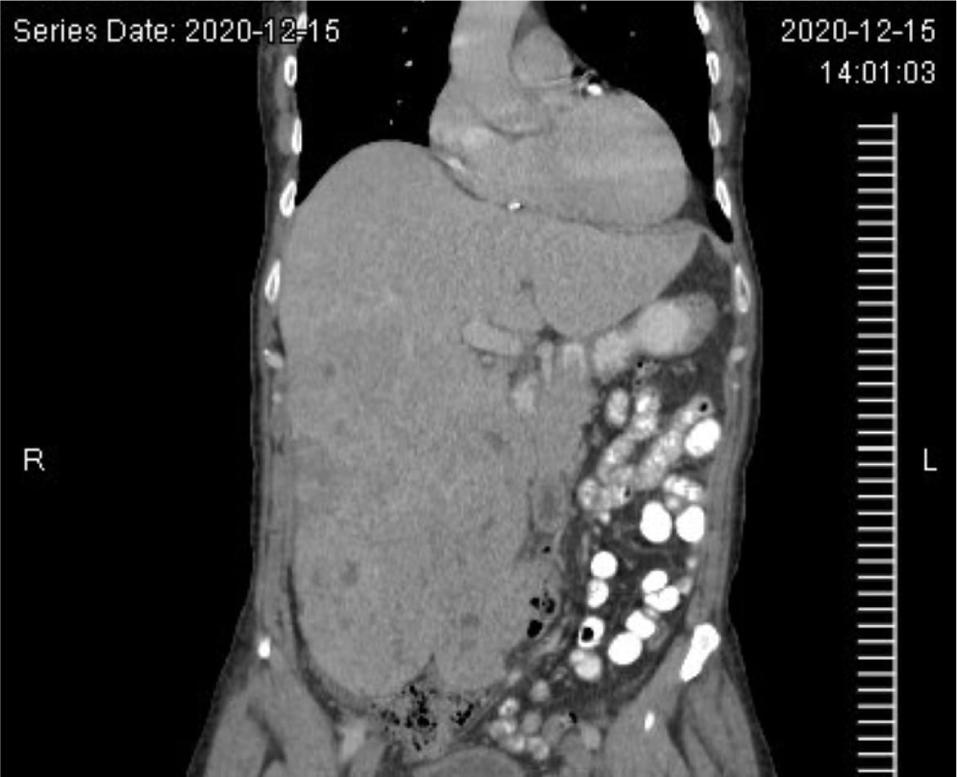

At 4 months follow-up from the VATS, a restaging CT scan demonstrated an enlarged liver with numerous low-density masses within the liver, including a conglomerate of masses within the right lobe of the liver, and an increase in the size and number of pulmonary nodules (Figure 4). The restaging CT also demonstrated the development of ascites in the pelvis and a probable tumor implant in the left peritoneal cavity, lateral to the psoas muscle. The patient was started on systemic temsirolimus, an mTOR inhibitor. Initially, after 3 months on temsirolimus, the patient demonstrated a dramatic improvement both clinically and radiographically. However, he ultimately stopped responding to temsirolimus. He was then transitioned to gemcitabine but unfortunately, the patient eventually passed away after this treatment alteration.

Figure 4: Abdominal CT image. CT image demonstrating massive tumor recurrence in the liver after surgical resection of primary tumor and prior to initiation of temsirolimus.